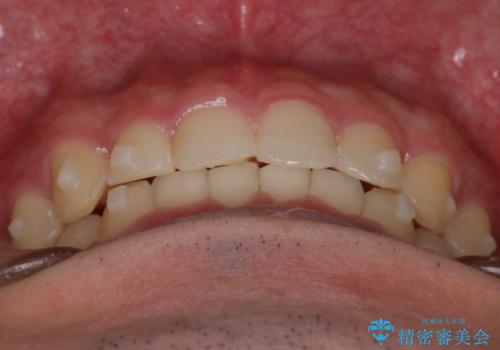

【インビザライン】前歯のガタガタと、前歯の噛み合わせが深いことを治したい。

- 前歯のガタガタと、前歯の噛み合わせが深いことを治したい。との主訴で来院されました。

シミュレーションを用いながら患者様と仕上がりについて相談しインビザラインにて治療を行いました。

仕上げは追加アライナーを数回利用しておこないました。